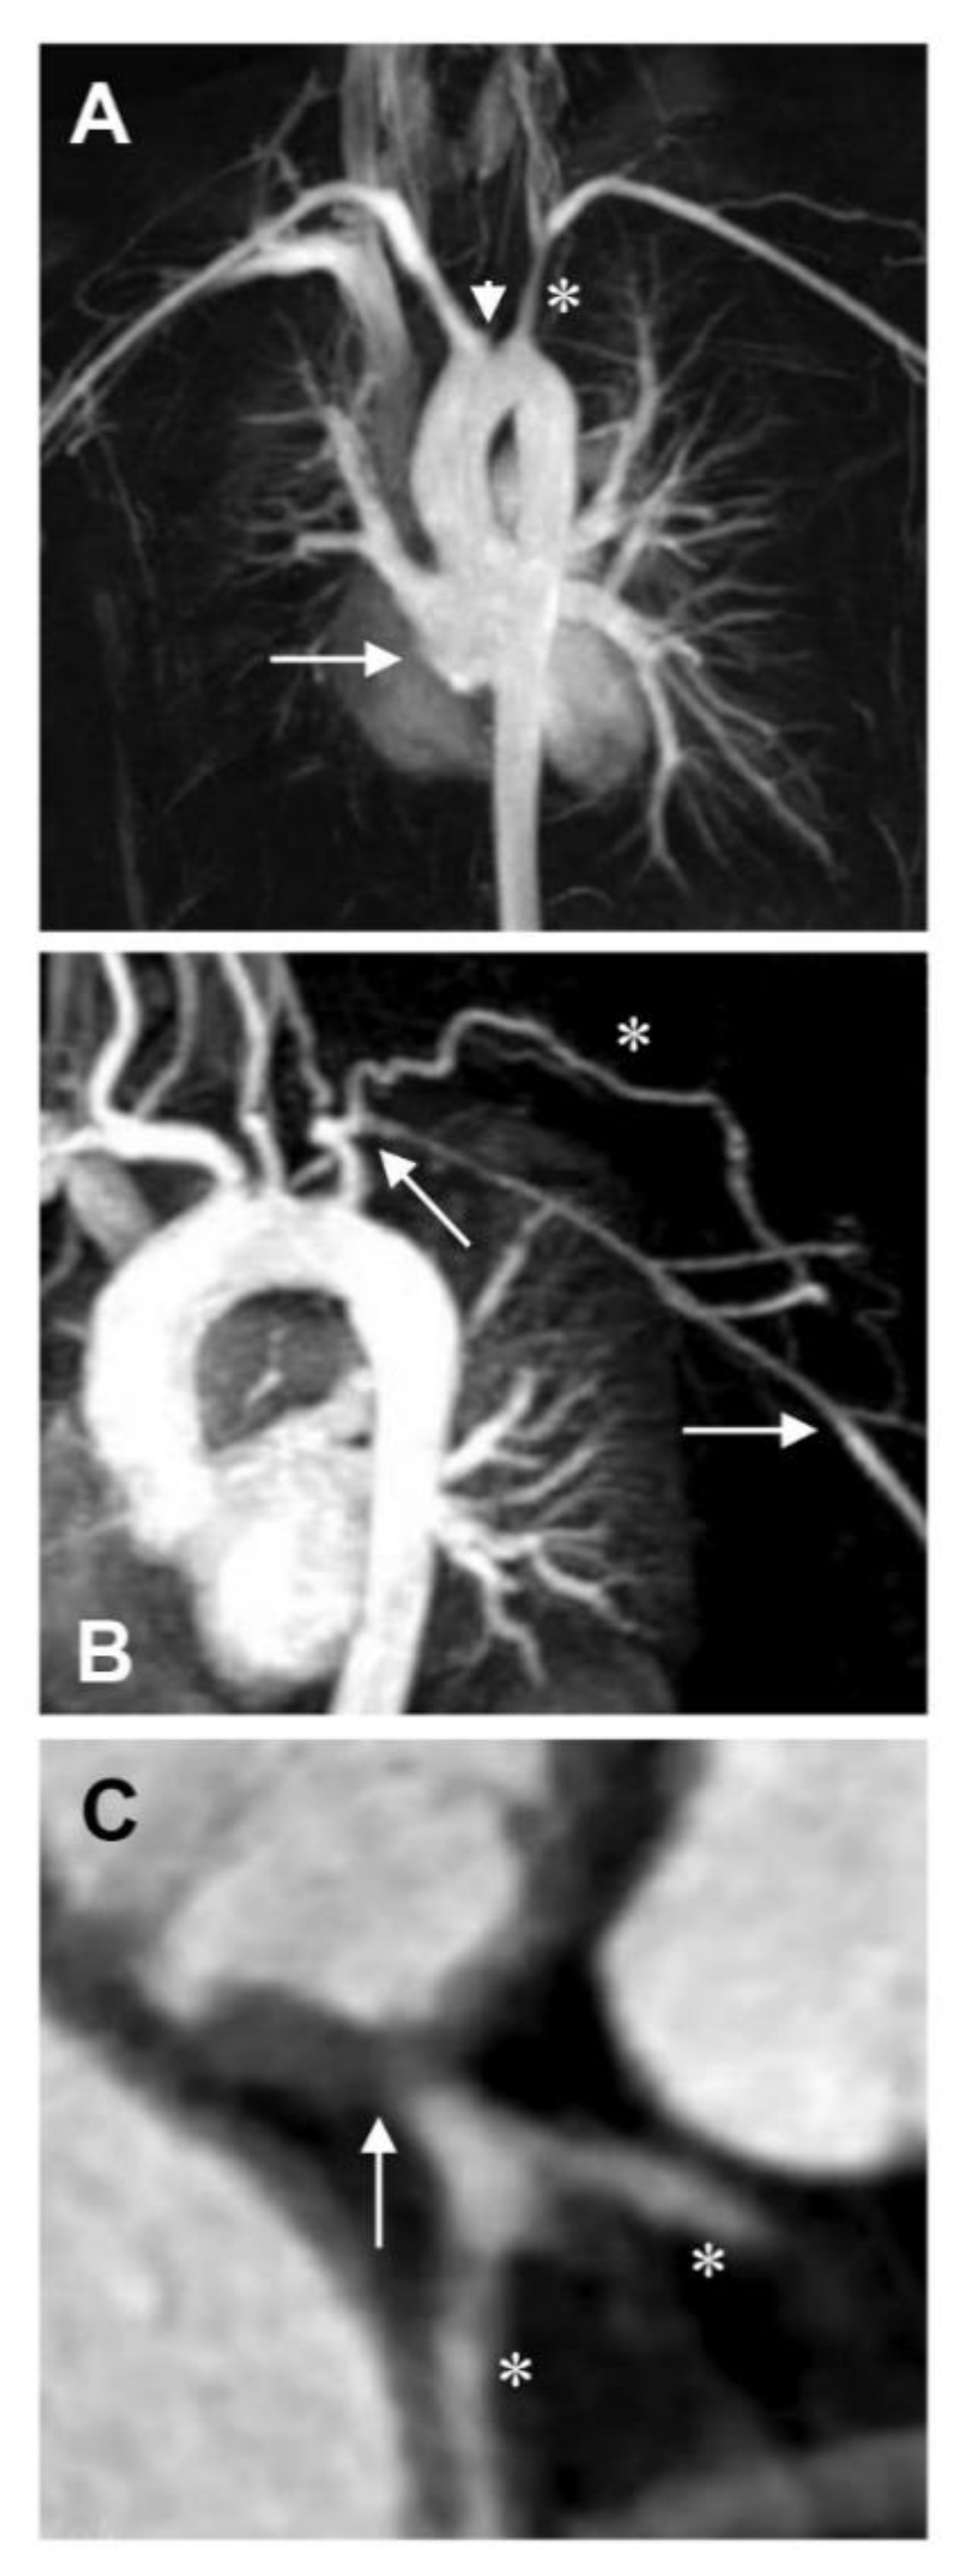

8.5. Visceral Arteries

9. Discussion